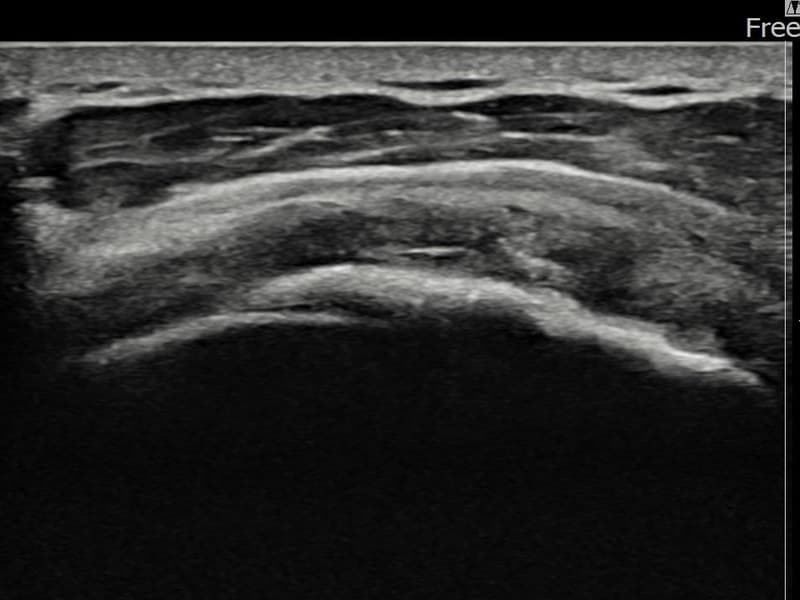

术后

术前超声确认左侧 冈上肌腱 광범위 部分撕裂,左侧冈上肌腱回声不连续伴肌腱缺损(15mm × 6mm (肌腱厚度约70%缺损))。术后超声显示撕裂部位充满再生组织,肌腱连续性恢复,回声模式正常化。

该患者持续肩痛。详细超声检查确认左侧 冈上肌腱 광범위 部分撕裂(缺损:15mm × 6mm (肌腱厚度约70%缺损))。在超声引导下实施非手术缩小缝合术。术后佩戴支具约4-6周,随后进行分阶段康复锻炼。随访超声确认肌腱连续性恢复、结构稳定,患者顺利回归日常生活。